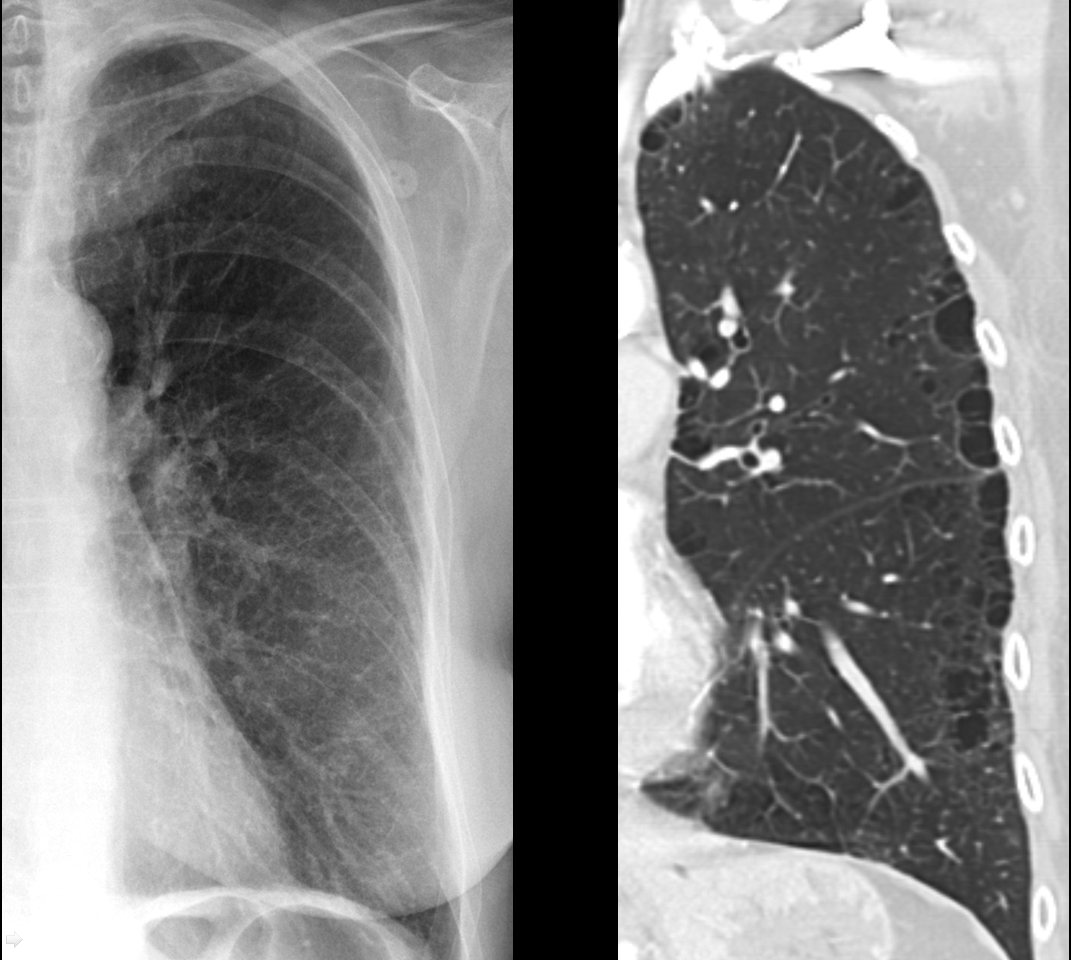

COPD

Subtle paraseptal emphysema